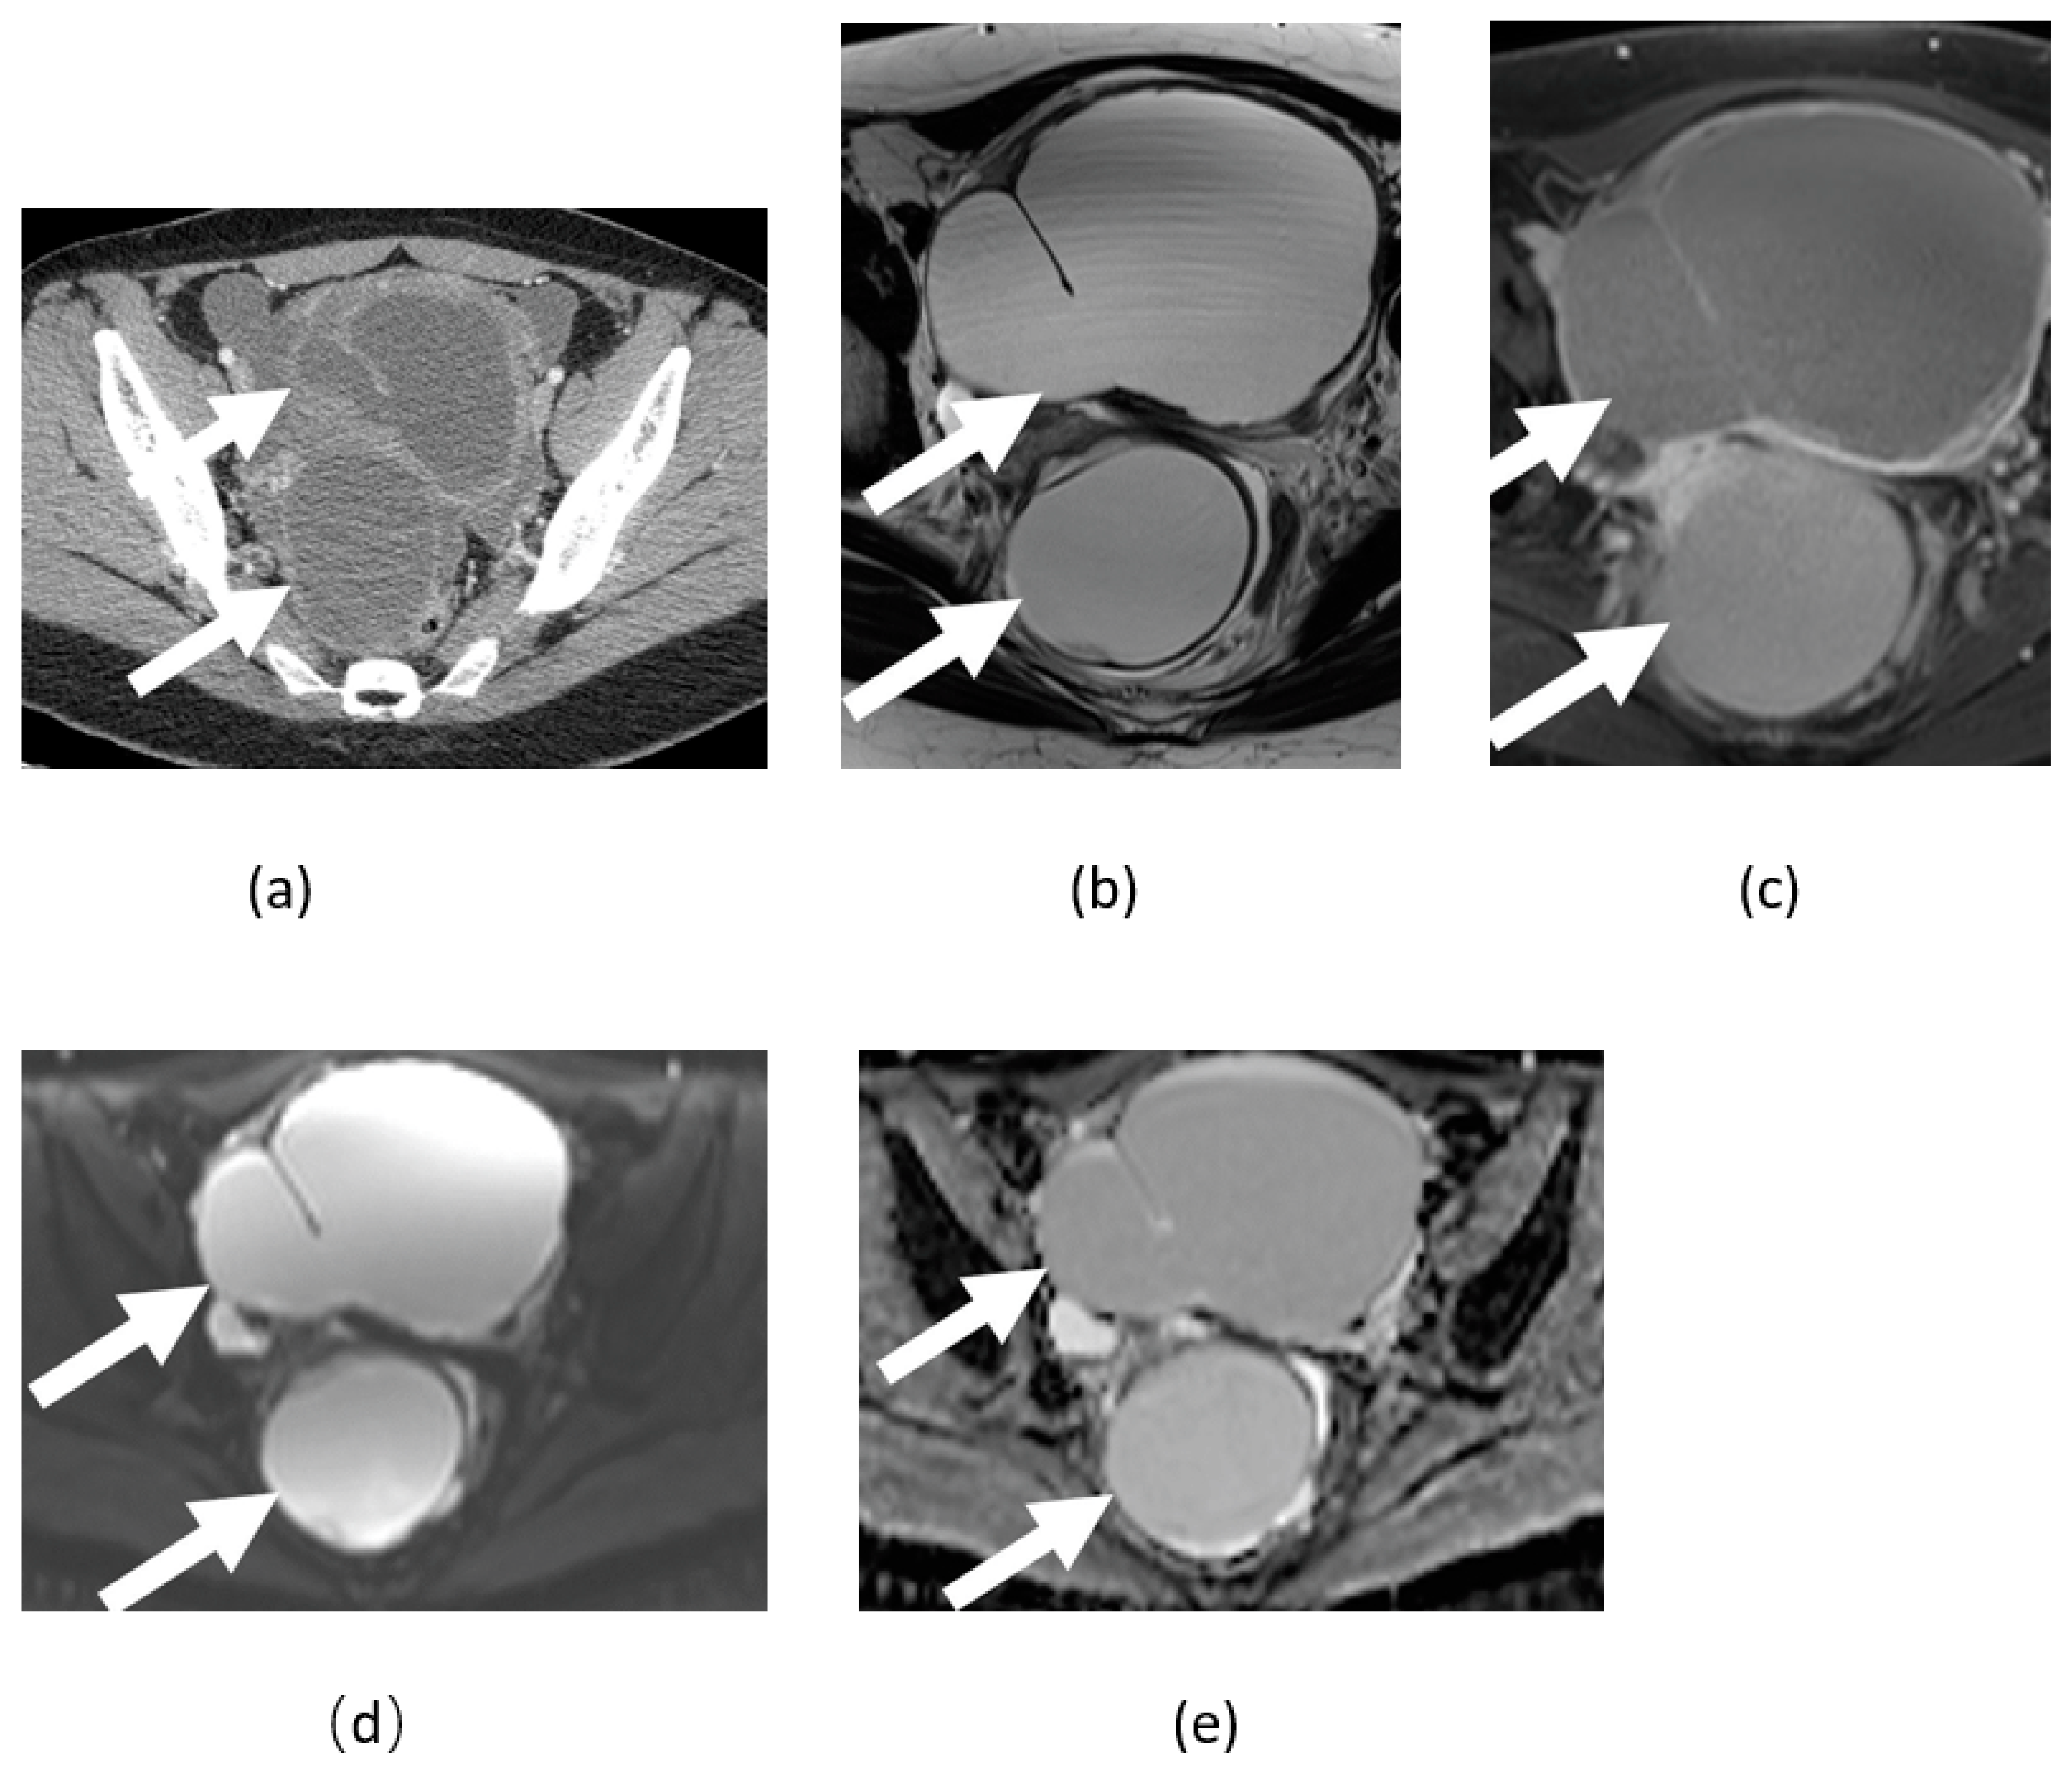

3.5. Mature Cystic Teratoma

3.6. Ovarian Fibroma, Fibrothecoma, and Thecoma